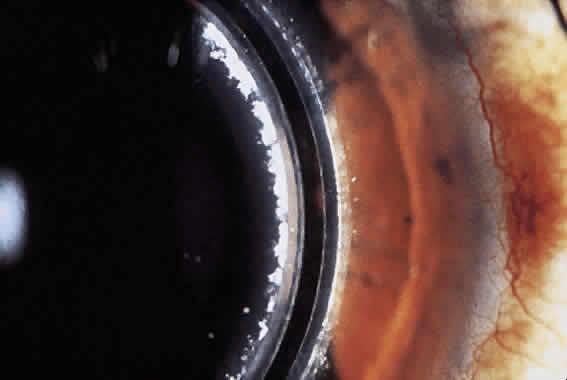

Another complication noted after surgery is epithelial ingrowth (Fig. 9). Controversy exists as to the exact cause, and thus terminology, of epithelial nests in the LASIK interface. One theory supports the idea that epithelium is caught on the keratectomy blade and planted in the interface (epithelial growth). Another possible explanation is that the epithelial cells migrate from the junction of flap (ingrowth).115 Whichever the case, the epithelial nests can proliferate, causing decreased vision secondary to obscuration of the visual axis or induction of irregular astigmatism.

Fig. 9. Slit-lamp photograph of epithelial nests in the corneal interface after laser in situ keratomileusis enhancement. A. This nest of epithelial cells were observed and exhibited no growth and no reduction of BSCVA. B. These nests demonstrated progression toward the visual axis and several attempts were made to remove them. Finally, after absolute alcohol treatment and scraping, the nests resolved. Final uncorrected visual acuity was 20/200, and best corrected acuity was 20/20 with a refraction of + 2.75 + 1.75 × 110.